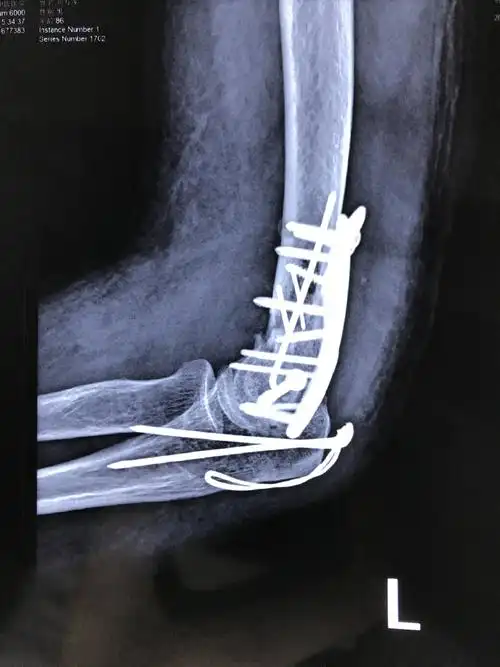

肱骨髁间骨折一例

辅助检查:x线,ct 临床诊断:左肱骨髁间骨折(iii型) 治疗经过:外院转